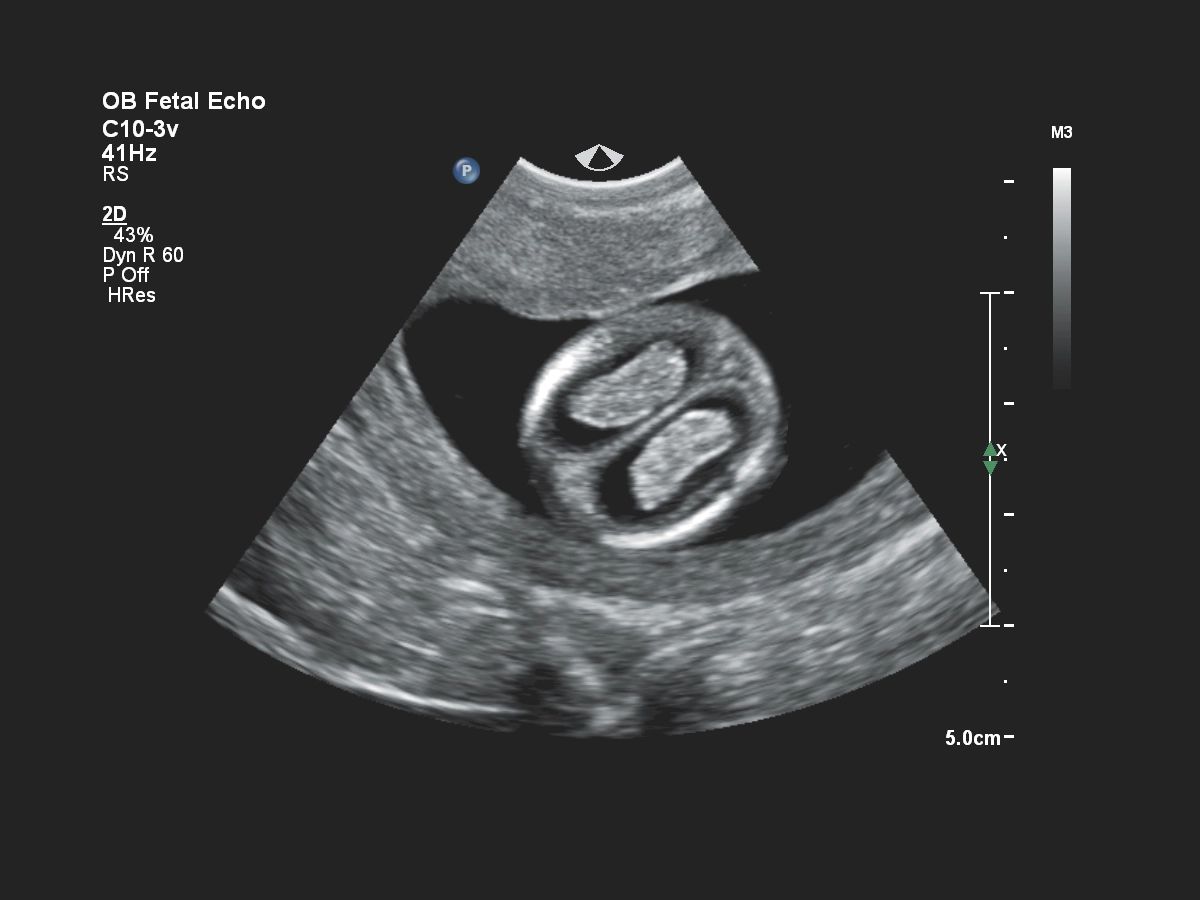

Функции для кардио-исследований

- Stress Protokol - стресс эхокардиография

- GI 3DQ - количественный анализ 3D

- TDI - тканевый допплер

- Strain Q - функция для оценки скорости движения стенок миокарда

- A2DQ - автоматическое распознавание границ камер сердца и расчет площади, объема левого желудочка и параметров систолы и диастолы левого желудочка, расчет фракционной площади, фракции выброса, максимальной скорости выброса, максимальной скорости быстрого наполнения и фракции предсердного наполнения

- aCMQ - Анализ параметров общей и конкретной сократимости камер сердца

- MVI - функция для точной визуализации микрососудов при помощи картирования прохождения контраста по сосудам

- Contrast Card - функция для отображения микропузырьков в миокарде при введении контраста для анализа микроциркуляции в ЛЖ

- Fetal Heart Navigator - функция для навигации сердца плода

- a2DQ LA - функция автоматического/полуавтоматического распознавания границ левого предсердия